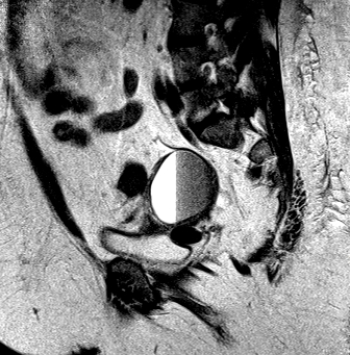

Male and Female Urinary Tract and Male Genital Tract